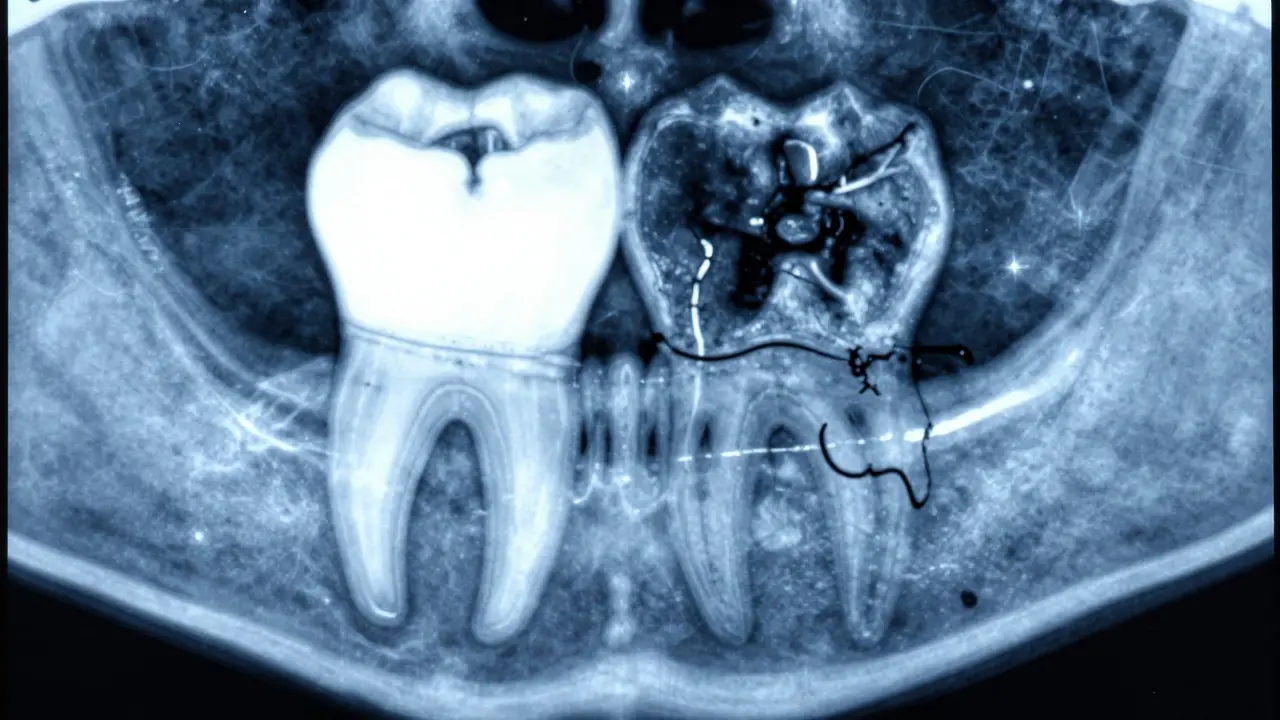

Stav okostice se kontroluje pomocí panoramového snímku nebo 3D tomografie. Dentisté hledají tři hlavní znaky:

- Hustota kosti kolem kořene - zdravá okostice je bílá a hustá na snímku

- Šířka kostního základu - pokud je užší než 2 mm, hrozí riziko selhání

- Průběh hranice mezi kostí a zubem - zdravá mez je ostrá, poškozená je rozmazaná nebo „vypálená“

Nejlepší způsob, jak zjistit, zda je vaše okostice zdravá, je digitální rentgenový snímek. Moderní dentální tomografie (CBCT) ukazuje kostní strukturu v 3D. Vizualizuje:

- Objem kosti kolem každého kořene

- Přítomnost zánětu nebo infekce

- Stupeň resorpce

V praxi to znamená: pokud máte metalokeramickou korunku, která vám slouží více než 10 let, měli byste ji každých 2-3 roky zkontrolovat pomocí tomografie. Většina lidí si to nechávají dělat jen při bolesti - ale už v té době může být kost poškozená trvale.